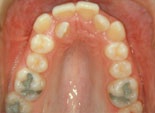

Trångställt bett

trångställt bett före behandling trångställt bett efter behandling

Före behandling av trångstätt bett Efter behandling av trångställt bett

Ett trångställt bett med för smal käke, i vy mot gommen. Således en kombination av en malocklusion och en utrymmesanomali. Om man behandlar liknande anomalier i rätt tid under ungdomsåren kan man till och med, som här, bredda käken med hjälp av tandreglering. Barnets egen växt hjälper till.